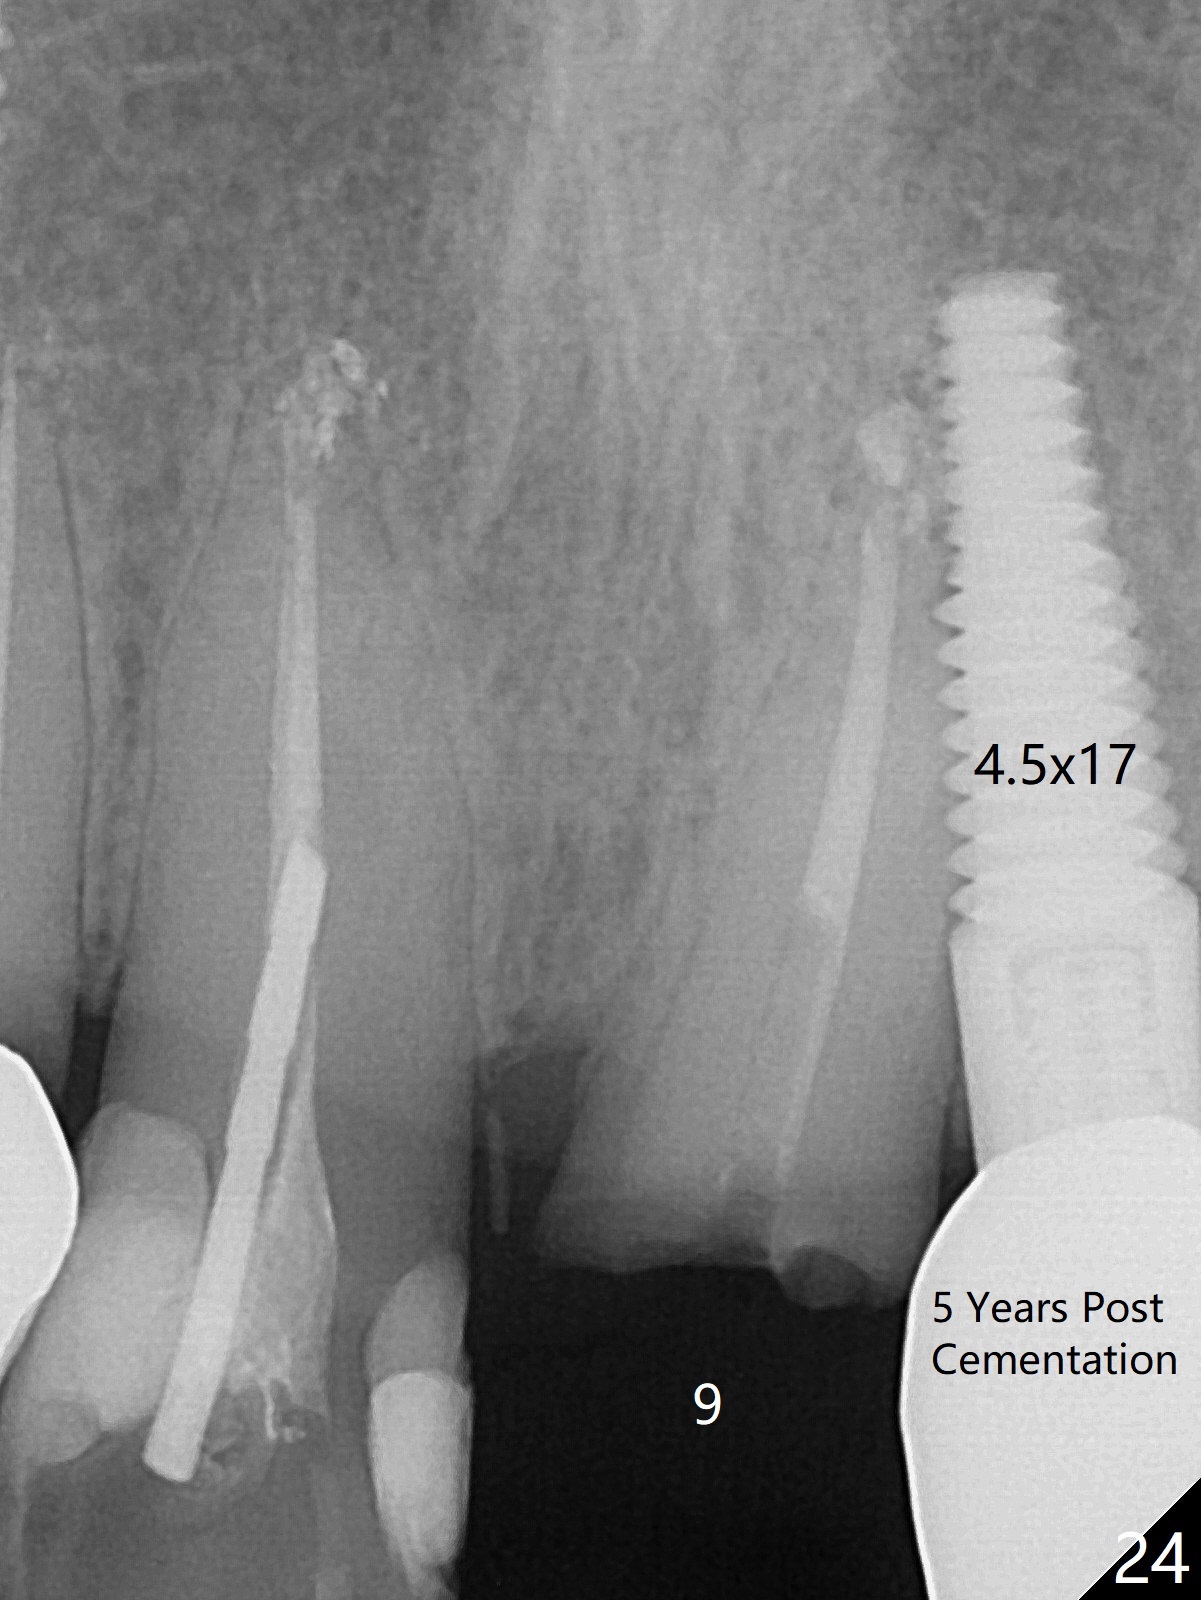

Six months post cementation, the tooth #9 becomes symptomatic. Is it possible that the implant at #10 is too close to the root of #9? It is asymptomatic after pulpotomy, but the tooth fractures equi/supragingivally. Two PAs taken while RCT show osteointegration at #10-12 (Fig.18,19). While the bone density increases at #10 regular implant, there is minimal bone loss around the 1-piece implants 13 months post cementation (18 months postop, Fig.20,21). The gingiva remains healthy 19 months post cementation (Fig.22). 76岁病人突然打电话说一个植牙牙冠松动,其实9号牙(自然牙)折裂,6,10-13号牙植牙好像没有骨质吸收(图二十三至二十五),10-13牙位牙龈健康(图二十六,行使功能五年)。9号牙牙冠重新粘固后,显示前牙深覆合,深覆盖(图二十七,二十八)。如果再次脱落需要植牙,选择一段式有助于植入和修复,因为植体和基台直径小。两段式植牙相对基台直径至少4,或者4.5毫米,前牙修复显得笨重。由于9,10牙根和植体接近,9号牙植体需要偏小而长,3x14或者15毫米(图二十九)。